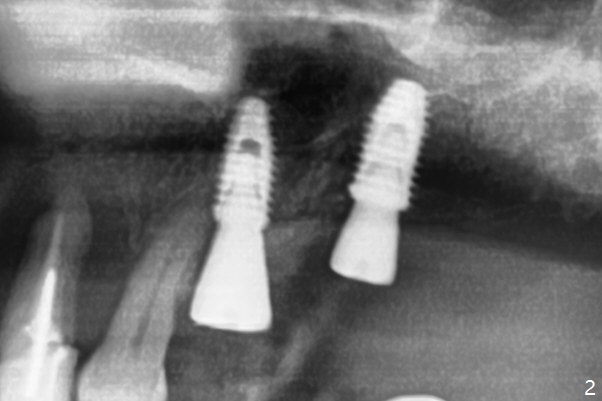

Immediately postop PA (Fig.1) and panoramic X-ray (Fig.2) show that the implant at #14 is close to the root of the tooth #13.  Clinic exam and CBCT (Fig.3,4) demonstrate a reasonable separation.  The trajectory of #14 osteotomy may be altered while using 2.8 mm round drill for 7-9 mm for sinus lift (free hand).  There is no bone loss 8 months postop (Fig.5).

#15 looks good as planned and #14 seems quite close to the neighboring tooth and quite off from the planed position.

I followed the steps faithfully.  As CT indicates, the implants are pretty parallel to each other.  The suspected step is sinus lift using reamer (free hand).  Initially I placed the drill pretty parallel to the crown #13.  Later more or less oblique.  When the guide returned, I had no option other than to follow the guide.  If the implant really touches the root, can I redirect free hand?